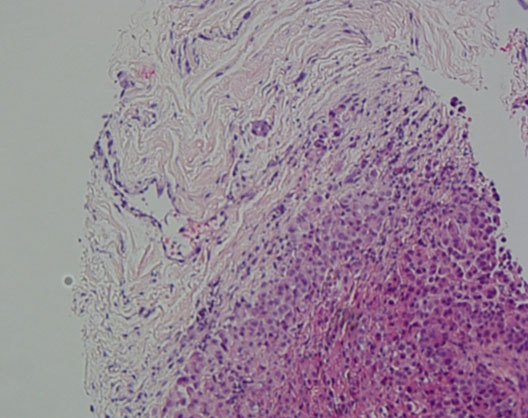

The patient was admitted to the hepatology inpatient service with consults from rheumatology, infectious disease, hematology, nephrology, pulmonology, and interventional radiology for a multidisciplinary approach to management. He underwent paracentesis followed by thoracentesis and an ultrasound guided peritoneal nodule biopsy. Turbid white chylous fluid (1200 mL) was removed from the left chest. The initial clinical impression from pulmonary was that the bilateral chylous effusion was likely secondary to superior vena cava syndrome and left brachiocephalic obstruction caused by lymphadenopathy. He was commenced on a low cholesterol diet and nutrition was consulted. Laboratory results from the first peritoneal tap showed atypical mesothelial cells indeterminate for malignancy (Figure 2). Subsequent thoracentesis (Figure 3) and paracentesis (Figure 4) specimens had higher cellular yield and revealed highly atypical mesothelial cells with high nuclear to cytoplasmic ratios and prominent nucleoli suggestive of malignant mesothelioma. Tumor cells were immunoreactive with Calretinin immunohistochemistry stain (Figure 5) which supported mesothelial origin rather than an epithelial origin (carcinoma). The diagnosis was further confirmed by an ultrasound guided peritoneal nodule biopsy which showed a consolidation of epithelioid tumor cells consistent with malignant mesothelioma, epithelioid type (Figure 6). Immunohistochemical staining of the omental biopsy for Ki 67 staining showed a high proliferative index > 10% (Figure 7). The tumor also contained foci of inflammatory cells including many plasma cells. These inflammatory cells could be reactive to the tumor or related to an underlying autoimmune or inflammatory process.

Figure 6: Omental core biopsy, malignant mesothelioma, epithelioid type, H& E stain, high power.

Share Image: